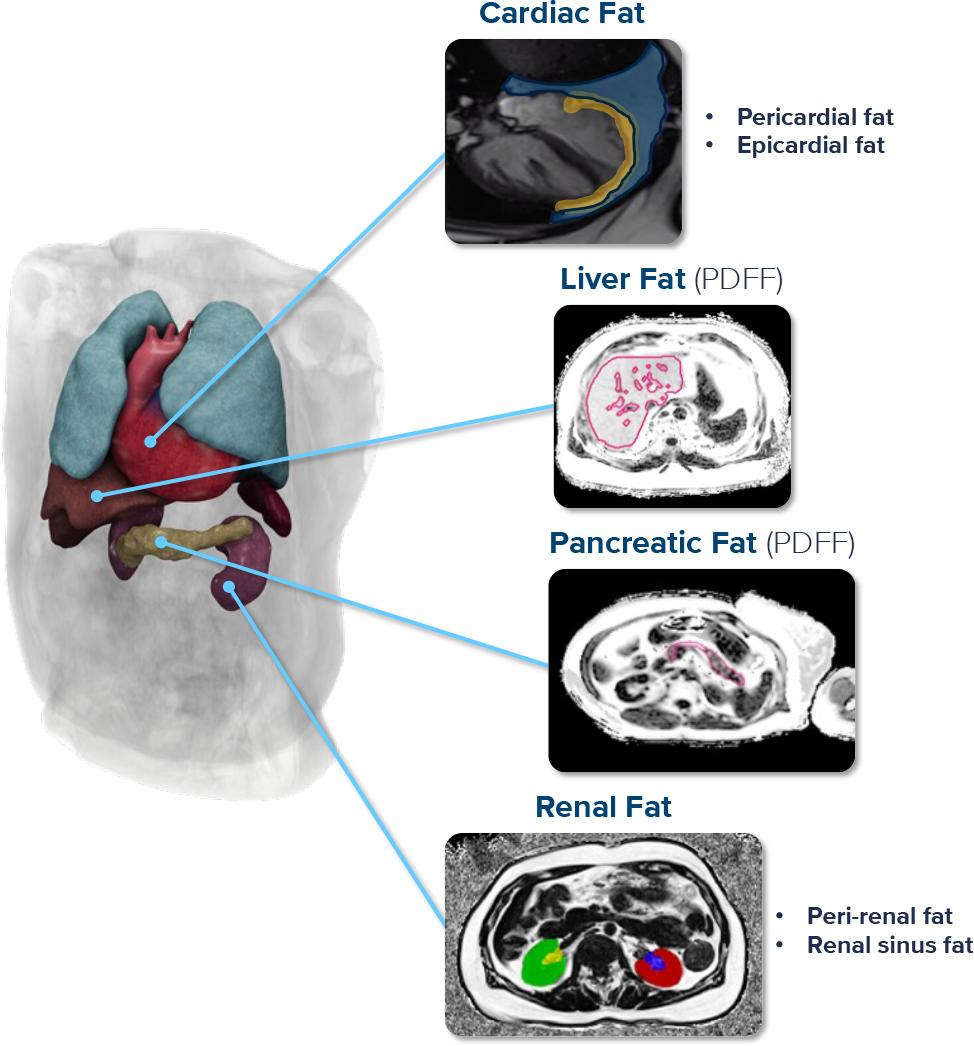

Multi-organ imaging and ectopic fat deposition

Emerging obesity and MetD treatments – including GLP-1 RAs – have demonstrated robust improvements in multi-organ health. Capture these systemic improvements through our multi-organ imaging portfolio.